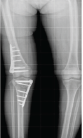

Follow-up mean MEPS scores improved significantly from 72.03 (SD ± 12.19, range 45–90) at 3 months to 84 (SD ± 13.39, range 50–100) at 6 months postoperatively to 98.56 (SD ± 13.06, range 55–100) at 1 year postoperatively. As per MEPS grading, postoperatively 3 months in 27 patients, 3.70% (n = 1) patients had excellent outcomes, 62.96% (n = 17) had good outcomes, 14.81% (n = 4) had fair outcomes, and 18.51% (n = 5) patients had poor outcomes. The MEPS grading postoperatively 6 months after surgery in 25 patients were as follows: 64% (n = 16) patients had excellent outcomes, 16% (n = 4) had good outcomes, 12% (n = 3) had fair outcomes, and 8% (n = 2) patients had poor outcomes. MEPS grading postoperatively 12 months in 25 patients showed that 80% (n = 20) patients had excellent outcomes, 16% (n = 4) had good outcomes, and 4% (n = 1) patients had poor outcomes. The final mean range of motion of operated upper limb was as follows: 28.5° of extension deficit (SD 9.07, range, 10°–40°), 117.5° of flexion (SD 13.18, range, 90°–130°), 70.9° of supination (SD 10.19, range, 40°–85°), and 65.5° of pronation (SD 9.54, range, 40°–80°). The final mean range of motion of the opposite normal upper limb was as follows: 6° of extension (SD 1.25, range 0–15), 136.54° of flexion (SD 4.80, range 125–145), 83.5° of supination (SD 10.19, range 75–90), and 78.62° of pronation (SD 9.54, range 70–85). The percentage deficit range of motion in the operated limb as compared to the normal upper limb was as follows: 7.4% deficit in extension, 16.2% flexion deficit, 17.77% deficit in supination, and 20% deficit in pronation. On radiological assessment, no elbow instability was seen in any elbow X-rays postoperatively assessed by a radiocapitellar line made by passing through the middle of the radius shaft which should pass through the capitellum on lateral elbow radiographs in any degree of elbow flexion. Out of 27 – 12 had complications, out of those 12 – three had elbow arthritis which is managed with symptomatic treatment with analgesics, they showed considerable relief of symptoms after 1 year, and two had heterotopic ossification for which supervised active elbow physiotherapy given along with tablet indomethacin, they attained a functional range of motion of the elbow, that is, 30–130° of elbow flexion at end of 1 year, three had radial nerve neuropraxia which recovered at end of 1 year, two patient’s had elbow stiffness and showed improved range of motion of elbow after 1-year follow-up and two patients suffering from ulnar nerve neuropathy which resolved on its own after 1-year follow-up. No other surgical intervention is required in any patient for any of the complications mentioned (Fig. 1-5).